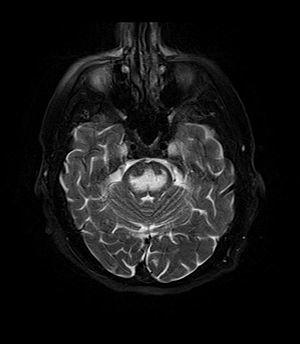

Axial fat-saturated T2-weighted image showing hyperintensity in the pons with sparing of the peripheral fibers, the patient was an alcoholic admitted with a serum Na of 101 treated with hypertonic saline, he was left with quadriparesis, dysarthria, and altered mental status

It can be diagnosed clinically in the appropriate context, but may be difficult to confirm radiologically using conventional imaging techniques. Changes are more prominent on MRI than on CT, but often take days or weeks after acute symptom onset to develop. Imaging by MRI typically demonstrates areas of hyperintensity on T2-weighted images.